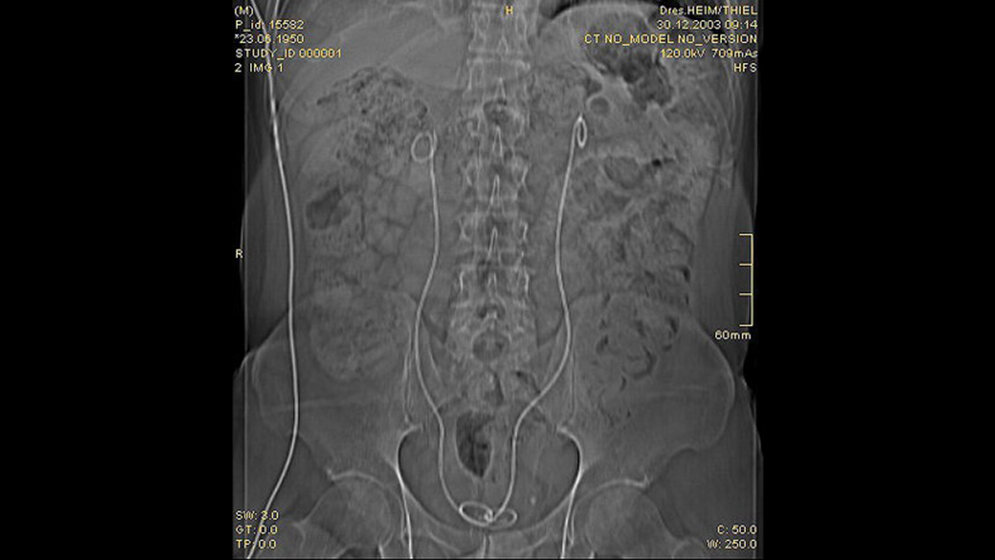

Der Morbus Ormond ist eine seltene Erkrankung, durch eine entzündliche Fibrose des Retroperitoneums charakterisiert. Die klinische Symptomatik ist unspezifi sch und kann abdominelle, Rücken- oder Flankenschmerzen beinhalten. Eine Komplikation kann durch Alteration der Harnleiter mit obstruktiver Nephropathie entstehen. Therapeutische Maßnahmen sind Glucocorticoide, Implantation einer Doppel-J-Schiene und die chirurgische Behandlung.